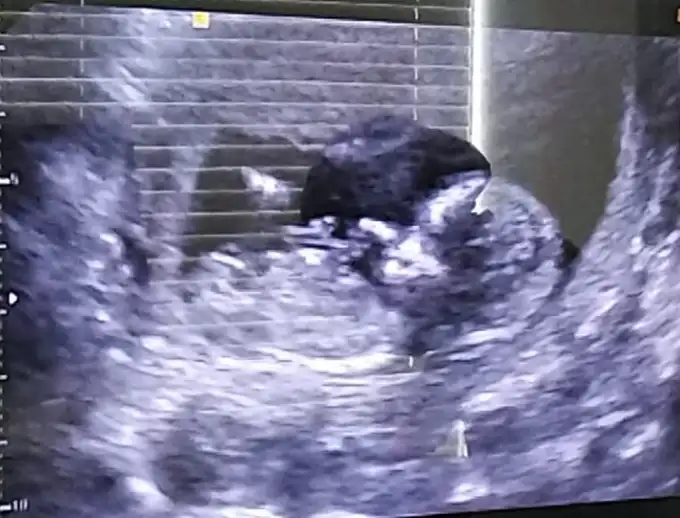

Merhaba benimkini de bakabilir misiniz?Şimdiden teşekkür ederim 🤗 Dr bana kız gibi dedi

Eklentiler

• IMG-20200702-WA0001.webp

IMG-20200702-WA0001.webp

31,3 KB · Görüntüleme: 81